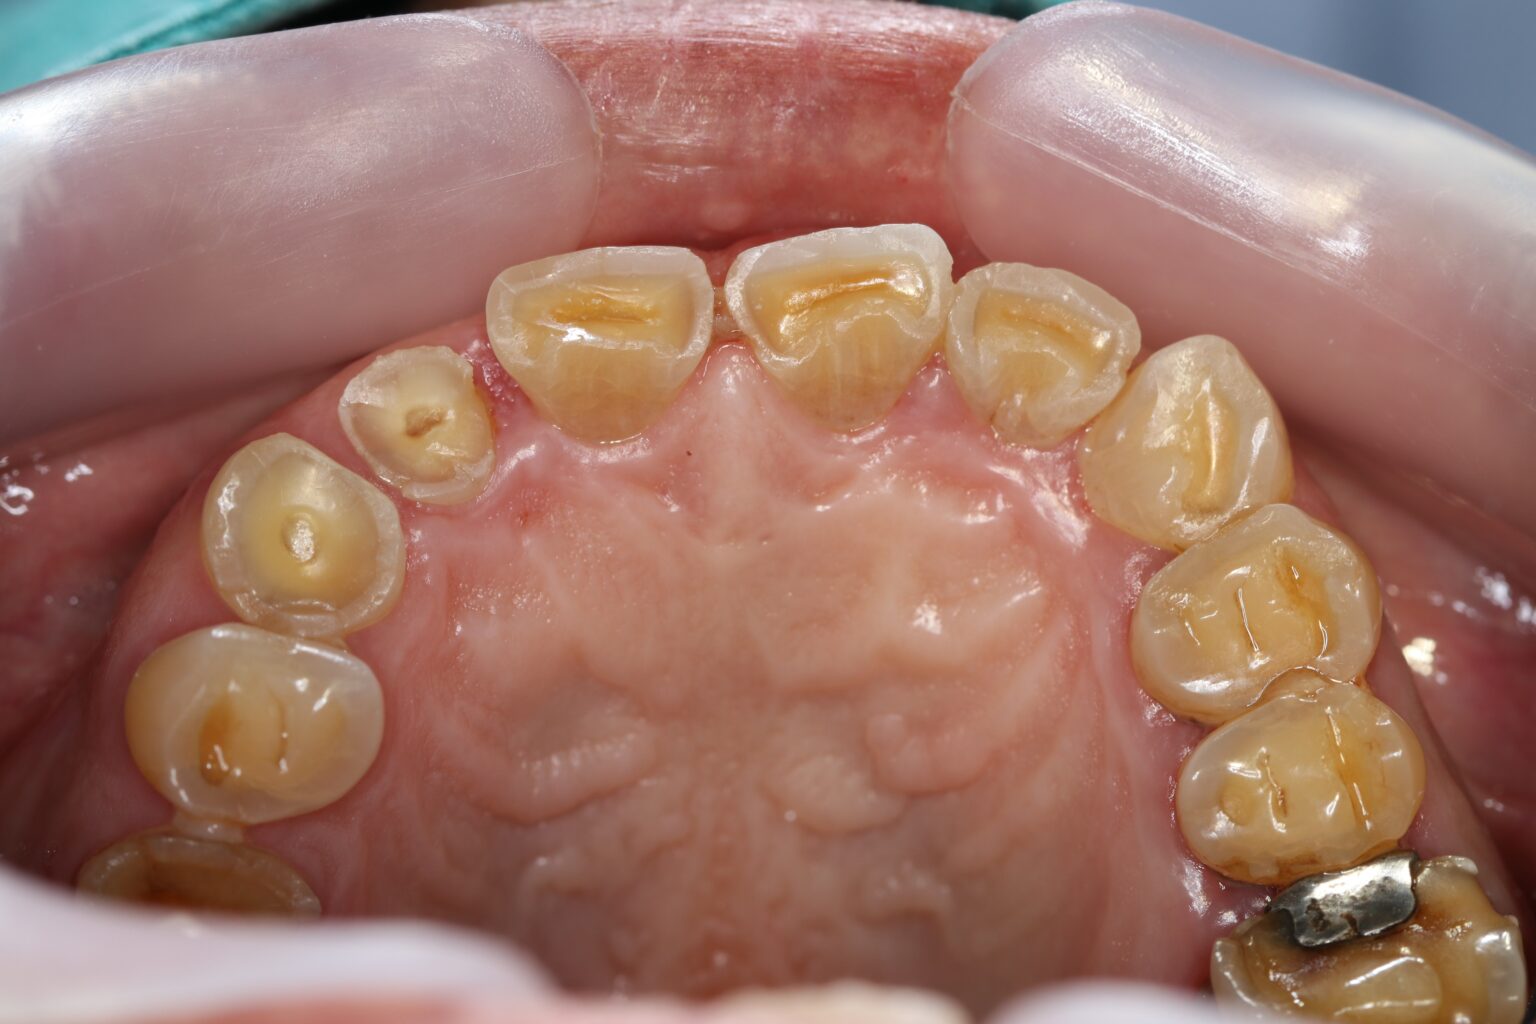

歯の摩耗と破折(はせつ)

歯の表面のエナメル質が削れ、中の象牙質が露出してしまいます。

また、強い力に耐えきれなくなった歯が、根元から真っ二つに割れてしまう(歯根破折)こともあります。

歯の先端がすり減って平らになっている

噛み合わせの面が真っ平ら、あるいは象牙質が透けて黄色く見えている。